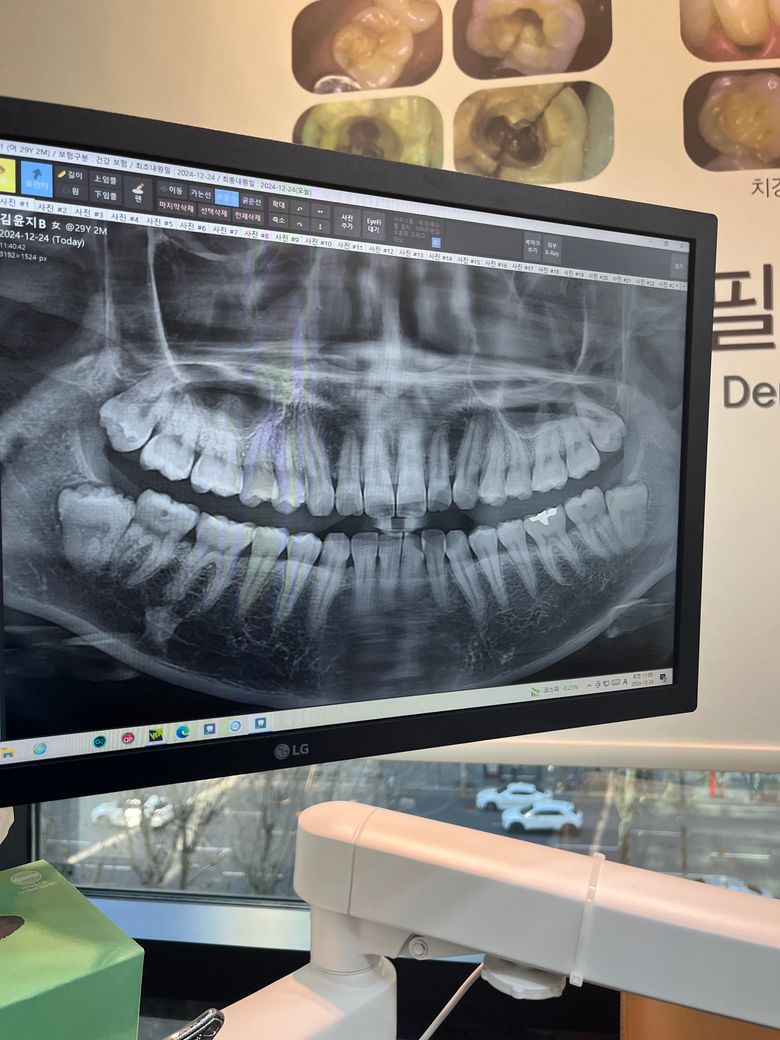

사진과 같은 하악 사랑니 발치 많이 아플까요?

상악은 쉬운데 하악은 매복이라 잇몸을 들어내야 한다던데 많이 아플까요?ㅠㅠ

• 1번 째 사진

크게 어려운 발치는 아닌거 같습니다. 수평매복은 아니니 너무 걱정은 안하셔도 될것같습니다.